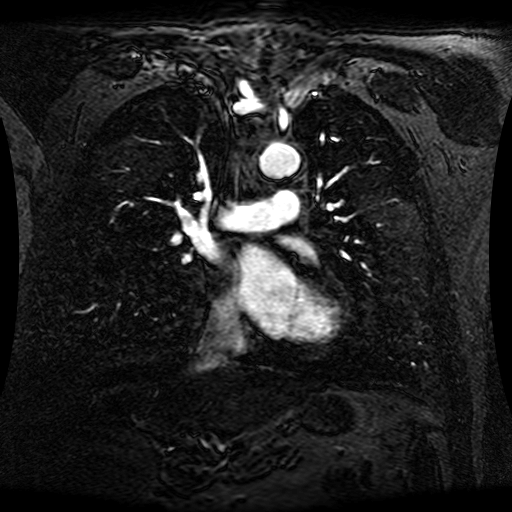

Data Description

These magnetic resonance angiography (MRA) images show coronal slices acquired from consecutive anteroposterior positions within the torso. The study was performed on a 1.5T General Electric (GE) Signa imaging system with gadolinium-contrast-enhancement for visualization of the cardiopulmonary vasculature. The pulse sequence used was a 3D time-of-flight fast spoiled gradient recalled acquisition in steady state (FSPGR, TR=6.3, TE=1.4, NEX=1, FOV = 40cm, slice thickness = 1.2mm).

This sample image contains 76 frames. It is available in DICOM format (E1154S7I.dcm), as an animated GIF (E1154S7I.gif), as .ogg, .mp4, .webm, and .swf animations (one of which is shown above), or as individual PNG-format frames (see below).